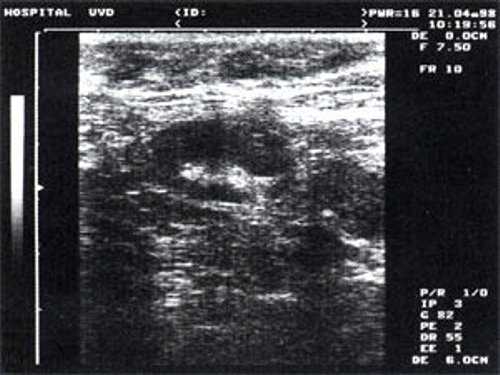

Практически во всех случаях дифференцировали лимфатический узел Кютнера (югулодигастральный), расположенный на границе средней и верхней трети шеи. Выявляемые лимфатические узлы имели размеры от 0,5 х 0,2 см до 2,3 х 0,8 см. УЗ-оценку производили после полипозиционного осмотра и нахождения самой длинной горизонтальной оси, что и принимали за максимальный поперечный диаметр. Большая часть лимфатических узлов (187) имели овальную форму с соотношением поперечного/переднезаднего более 1 (рис. 1 - 3). Тенденцию к округлению имели 30 лимфатических узлов, соотношение поперечного/переднезаднего приближалось к 1.

Рис. 1. УЗ-томограмма увеличенного реактивно измененного лимфатического узла: а - на фоне аденовирусной инфекции, б - после проведения противовоспалительного лечения